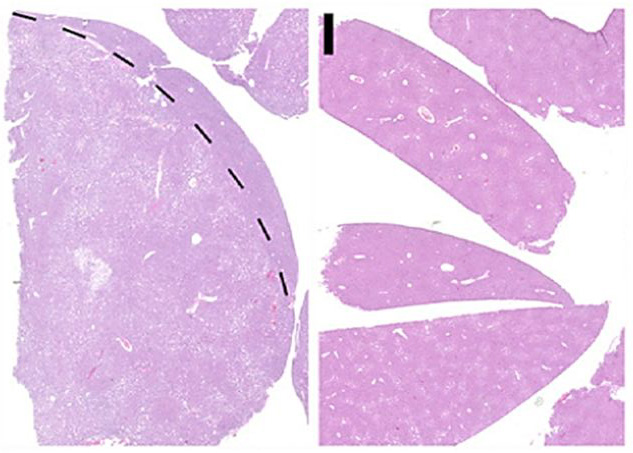

Leberkrebs. © Heikenwälder/DKFZ

Beide Krebserkrankungen sind unterschiedlich  und werden auch unterschiedlich behandelt. Als entscheidend für die Entwicklung der jeweiligen Krebsart erwies sich die Umgebung der Krebszellen, insbesondere die spezielle Form von Zelltod, die in der direkten Umgebung der Zellen auftrat. Die Wissenschaftler konnten zeigen, dass Vorstufen von Krebszellen, in deren Umgebung Zellen durch Apoptose - den klassischen Zelltod - zugrunde gingen, sich zu einem Leberzellkarzinom entwickelten. Angehende Krebszellen, in deren Umgebung Zellen durch Nekroptose absterben, führten zu einem Gallengangskarzinom. Bei der Nekroptose löst sich die Zellhülle auf und der Zellinhalt verursacht Entzündungen in der Umgebung der Krebszelle, während sich beim klassischen programmierten Zelltod kleine Vesikel bilden, die vom Immunsystem beseitigt werden.

Die Ergebnisse konnten sowohl im Mausmodell als auch an humanen Gewebeproben verifiziert werden. Krebsforscher Xin Wei Wang vom amerikanischen Laboratory of Human Carcinogenesis (Center for Cancer Research, National Cancer Institute, Bethesda), steuerte dazu wichtige humane Analysedaten bei und Oliver Bischof, einer der weltweit führenden Epigenetiker vom Pariser Institut Pasteur (Laboratory of Nuclear Organization and Oncogenesis), konnte aufzeigen, wie die Mikroumgebung auf die Krebszelle einwirkt.